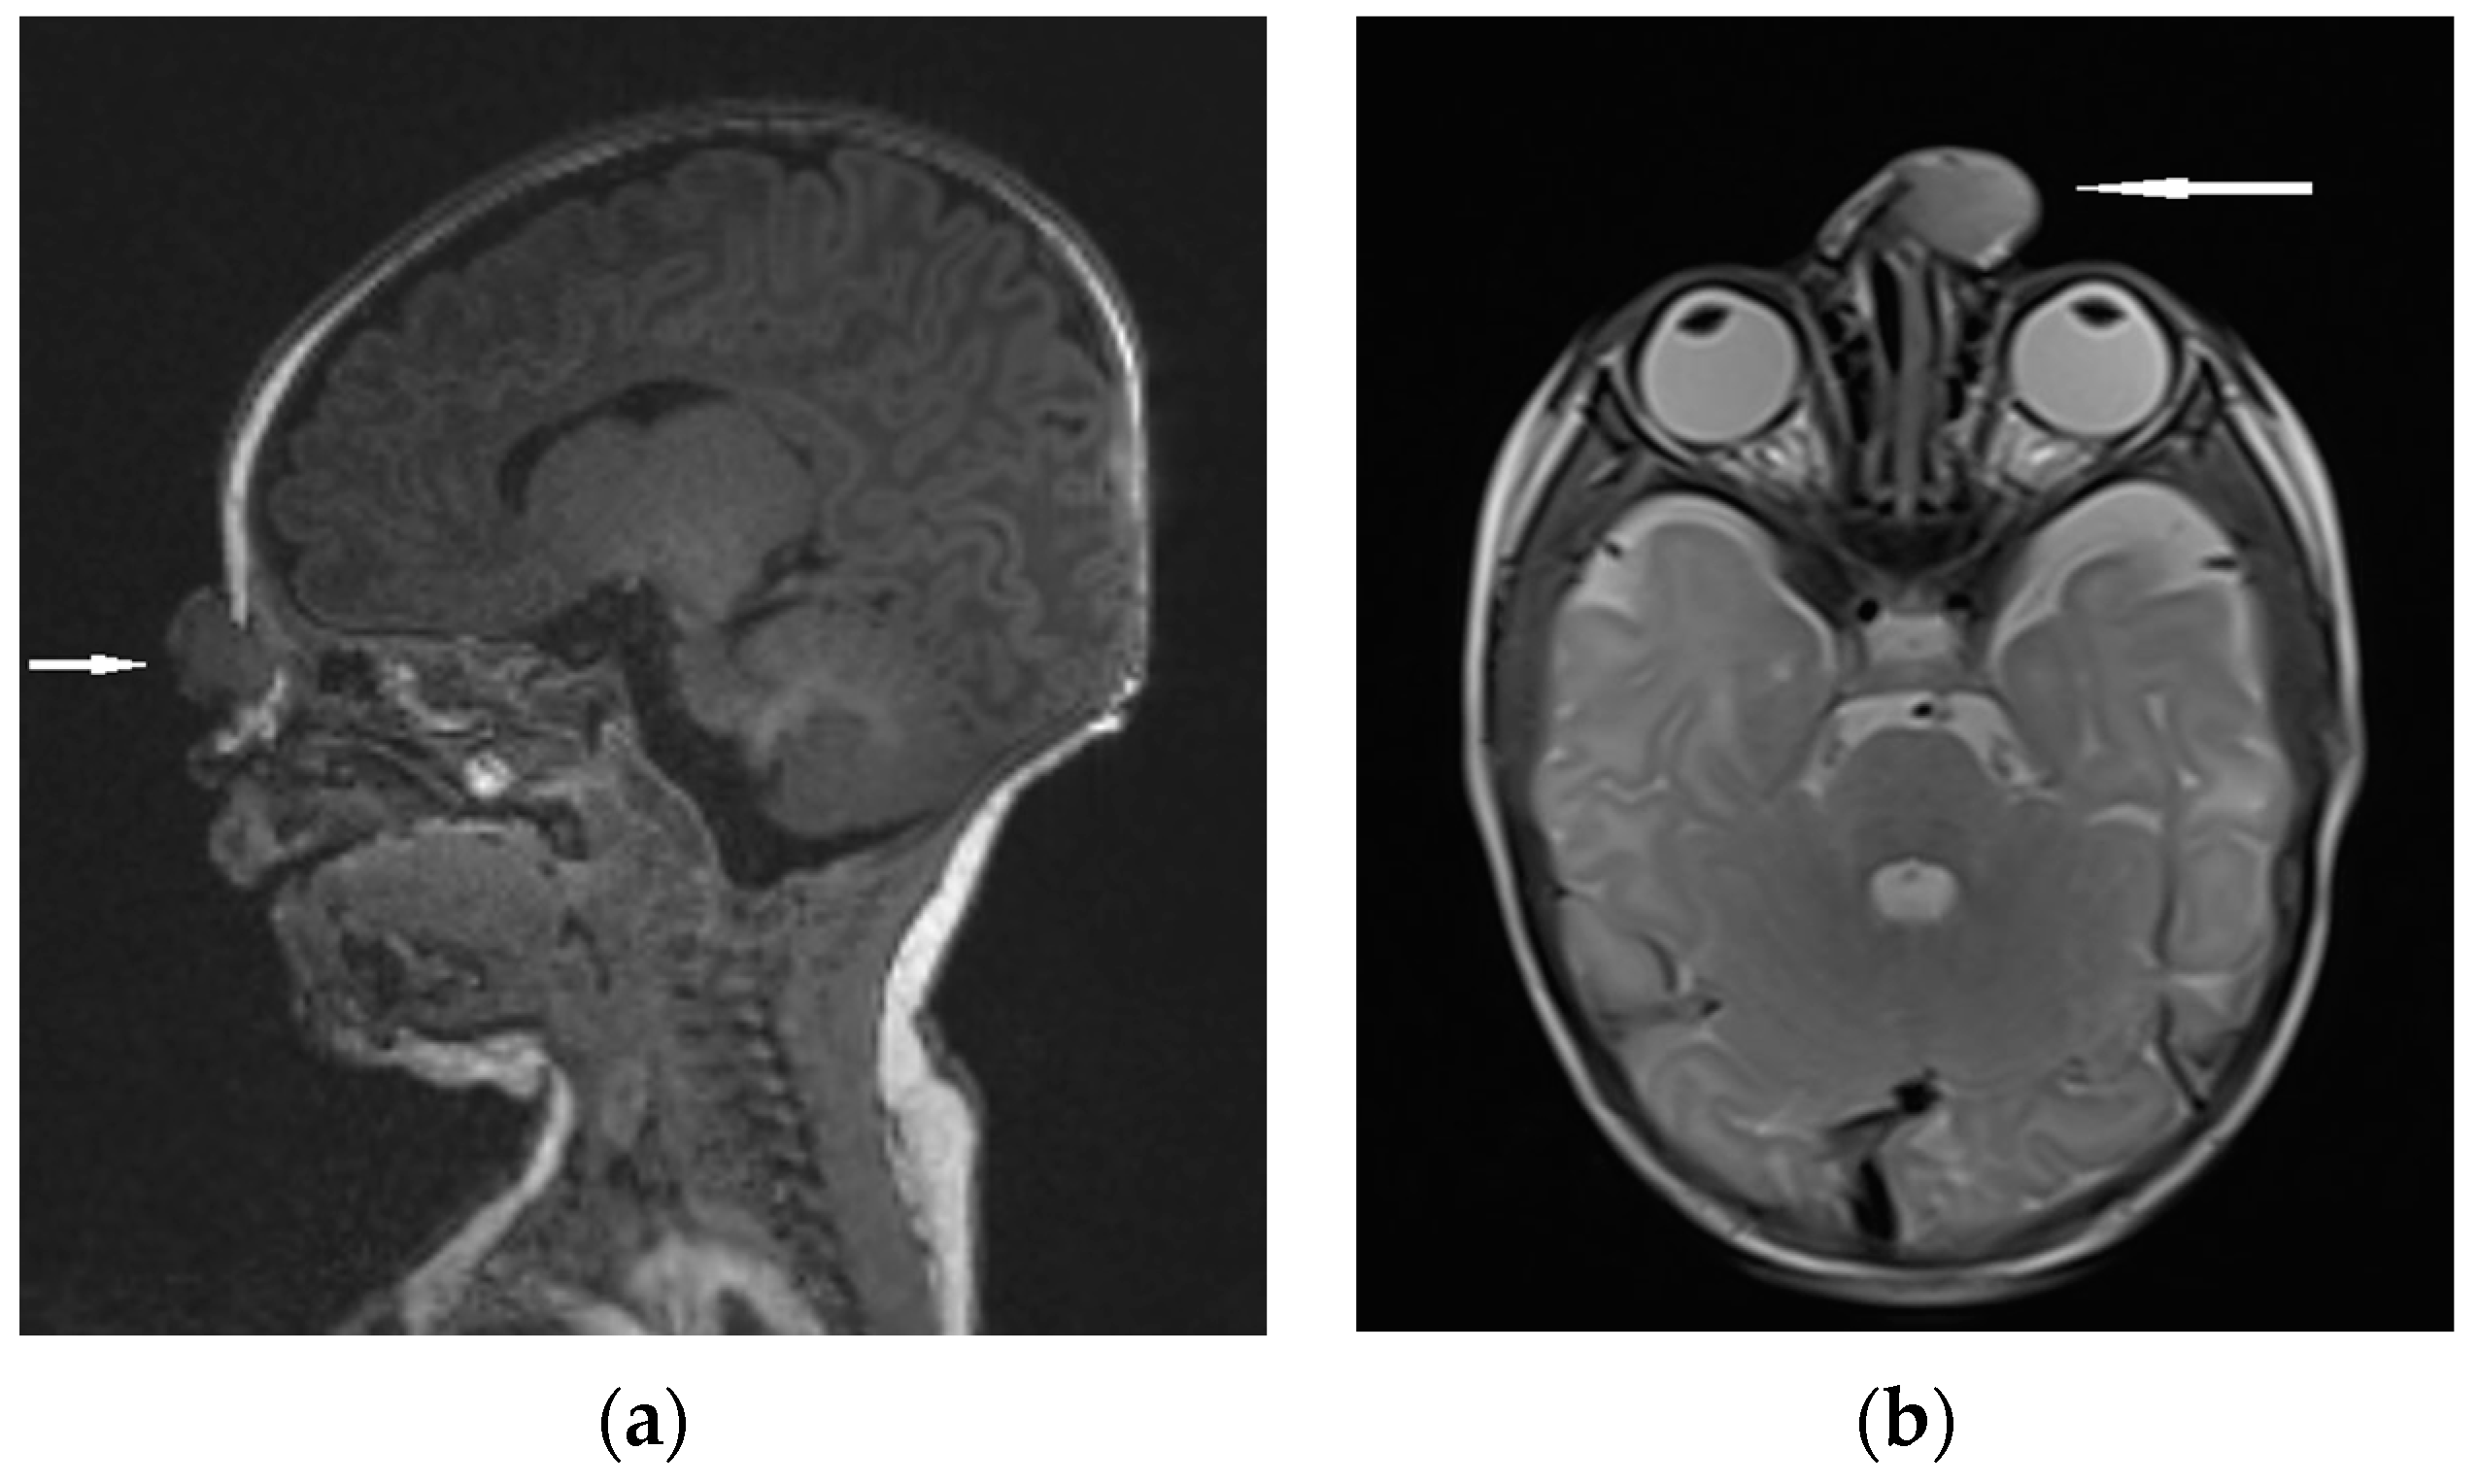

| Radiological characteristics | CT | No correlation between the particular location of the sinus ostium or cyst and the presence of intracranial extension; bifid crista galli and widening of foramen caecum (suggestive of intracranial extension); dermoid cyst—density of fat; epidermoid cyst—density of water | Bony defect may be revelaed | Developmental bony defect of the skull base |

| MRI | Variable signal intensity depending on the protein content; fat-suppressed T1-weighted images—differentiation between skull base defects and enhancing non-ossified cartilage of anterior cranial fossa; DWI—typically high-signal-intensity lesion with corresponding low signal intensity on ADC maps | Discontinuity with the brain parenchyma; variable visualization of a fibrous stalk connection to CNS; well-circumscribed, rounded, or polypoid mass—isointense or rarely hypointense to gray matter on T1-weighted imaging; neural tissue—more hyperintense on T2-weighted images to normal brain parenchyma in most cases; dysplastic tissue usually corresponds with no enhancement or moderate enhancement; noticeable enhancement at the lesion periphery | Herniation of intracranial tissue and its continuity with the brain | |